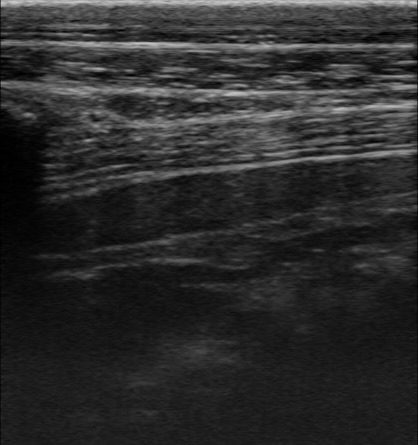

比較のため、隣にいた健常牛でも同じ部位で撮影してみます。

健常牛

こうしてみると、先に見た牛に異常があることが一目瞭然ですね!